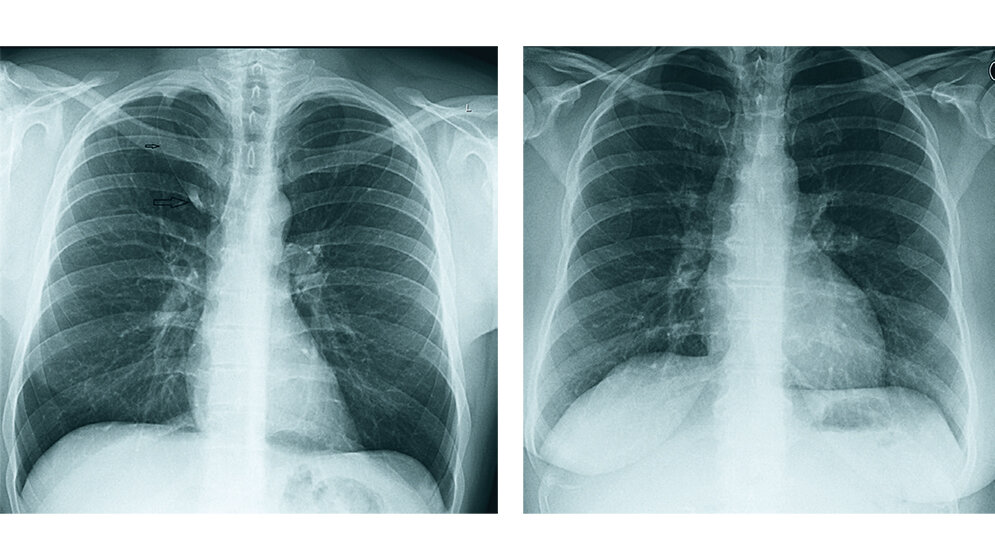

Die Pleura ist in entzündliche, neoplastische und traumatische Erkrankungen involviert. Es wird die Diagnostik der Anomalie der V. acygos und Pleura mit unterschiedlichen bildgebenden Techniken beschrieben.

The pleura is commonly involved in inflammatory, neoplastic and traumatic diseases. The article describes the diagnostic of the abnormality of V. acygos and pleura in different imaging techniques.